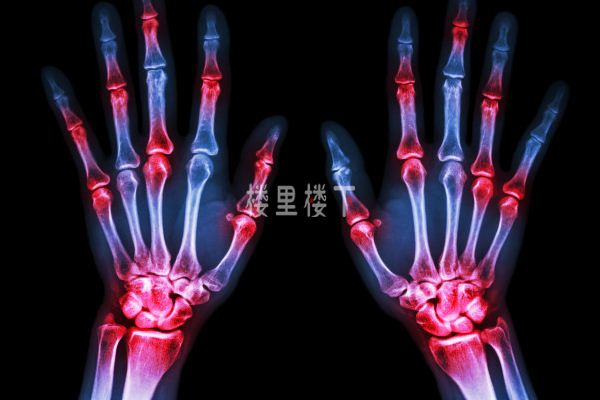

痛風(fēng)是一種非常痛苦關(guān)節(jié)炎類疾病,不限年齡段且高發(fā)于男性,具體痛風(fēng)的由來(lái)大家可以去網(wǎng)上搜索小曹這里就不去細(xì)說(shuō),簡(jiǎn)單來(lái)說(shuō)就是我們體內(nèi)的嘌呤物質(zhì)因?yàn)樾玛惔x絮亂引發(fā)尿酸合成的增加或排出減少,最終造成高尿酸血癥且以鈉鹽的形式沉積在關(guān)節(jié)軟骨等部位引發(fā)痛風(fēng),通過(guò)堅(jiān)持讓血尿酸降低并維持在合理水平,比如有痛風(fēng)石的低于300μmol/L,沒(méi)有痛風(fēng)石的低于360μmol/L以下,這樣就可以讓痛風(fēng)較少發(fā)作甚至達(dá)到康復(fù)目的。